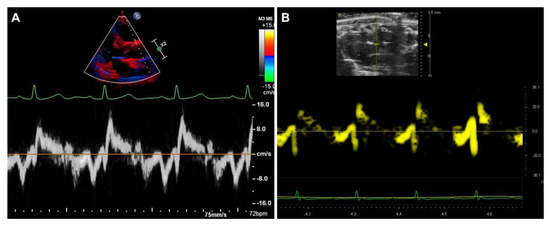

In addition to detecting the blood flow within the aorta, Doppler signals can also be collected from tissue and recorded by TDI, either as spectral or color displays, which can be used to measure tissue stiffness with the velocities and strain rate of the tissue motion. The image acquisition of the aorta by TDI is similar between humans (Figure 8A) and rodents (Figure 8B).

Figure 8. Representative images of the aorta and the waveforms by tissue Doppler imaging. The segmental velocity information of the anterior wall of the aorta in human (A) and mice (B).